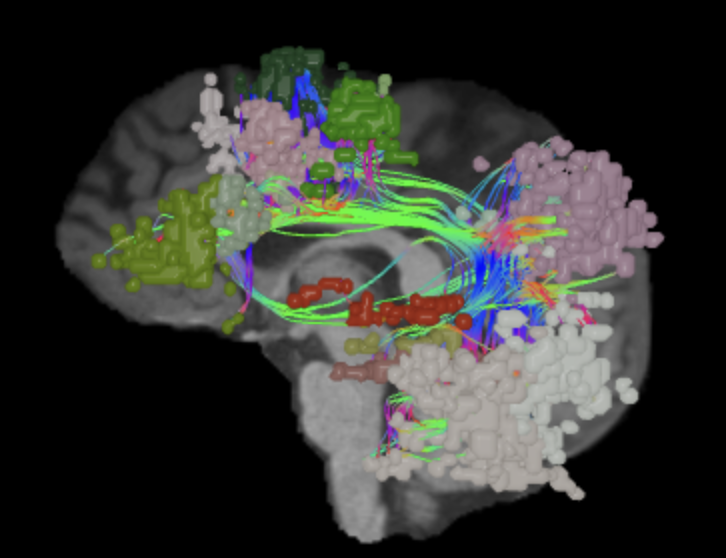

A: lateral-medial

B: anterior-posterior

C: superior-inferior

DTI image |